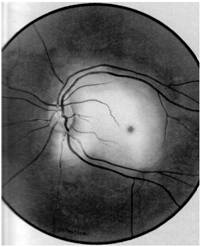

Corp strain intraocular

(pe traiect se observa plaga corneeana, gaura in iris,

cataracta localizata pe traiectul cristalinian)

Imaginea ecografica a corpului strain

(localizat in polul posterior al globului, la 3 mm de retina)

Uneori diagnosticul de corp strain intraocular este facilitat de evidentierea portii de intrare, sub forma unor leziuni corneene penetrante vizibile biomicroscopic, adiacente unor leziuni iriene -gauri in iris si cataracta localizata, care traseaza traiectul corpului strain in interiorul ochiului. Daca examenul fundului de ochi poate fi efectuat, acesta poate sa puna in evidenta corpul strain la nivelul vitrosului sau retinei (vezi plansa).